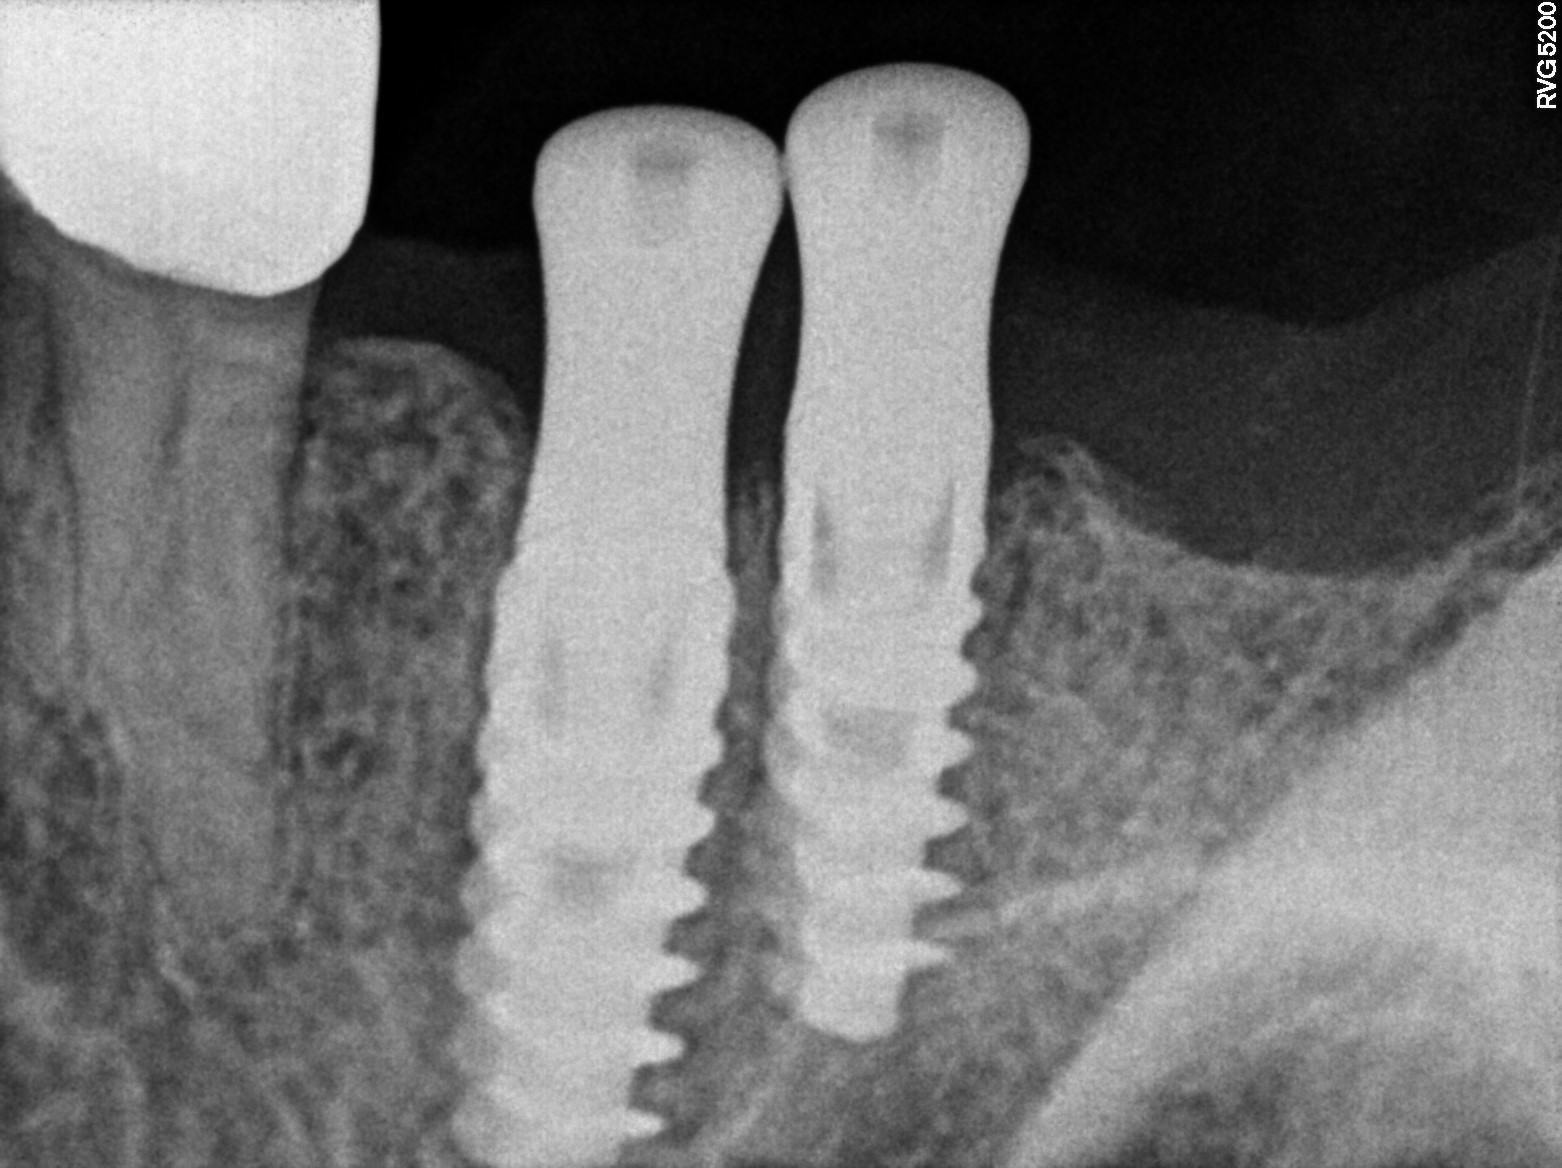

Dental Radiographs FHIR: DocumentReference · LOINC 24641-7

R55.jpg

24641-7